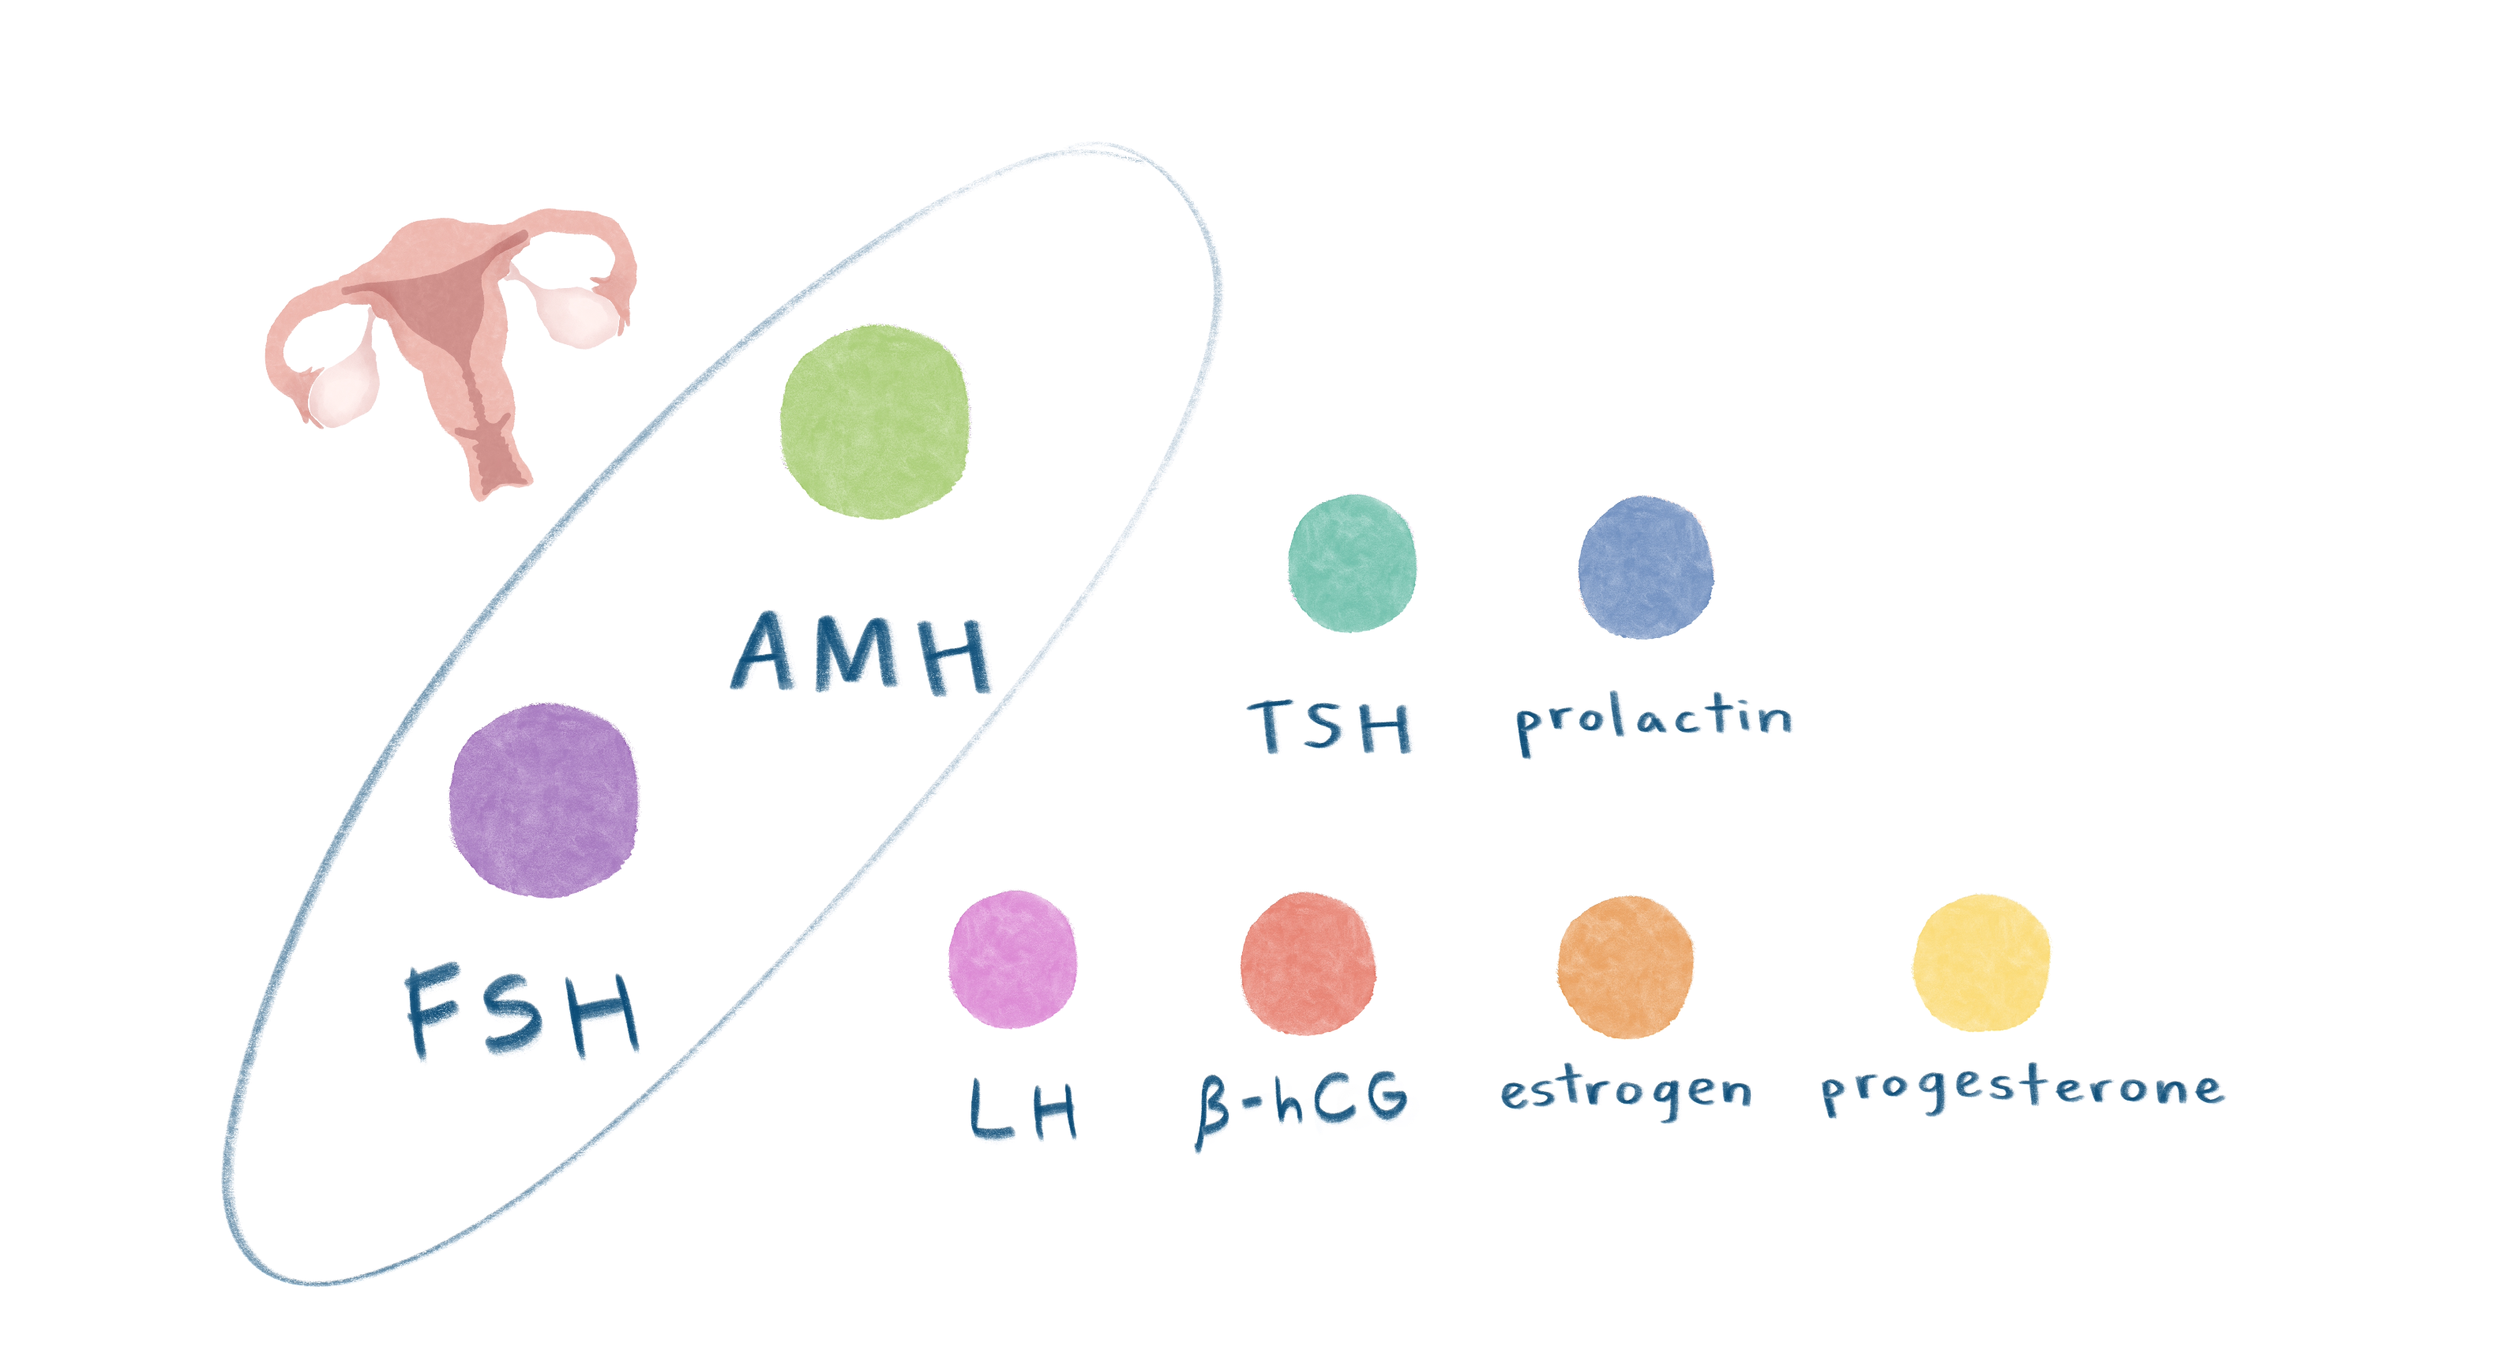

Fertility hormones

Fertility Hormones